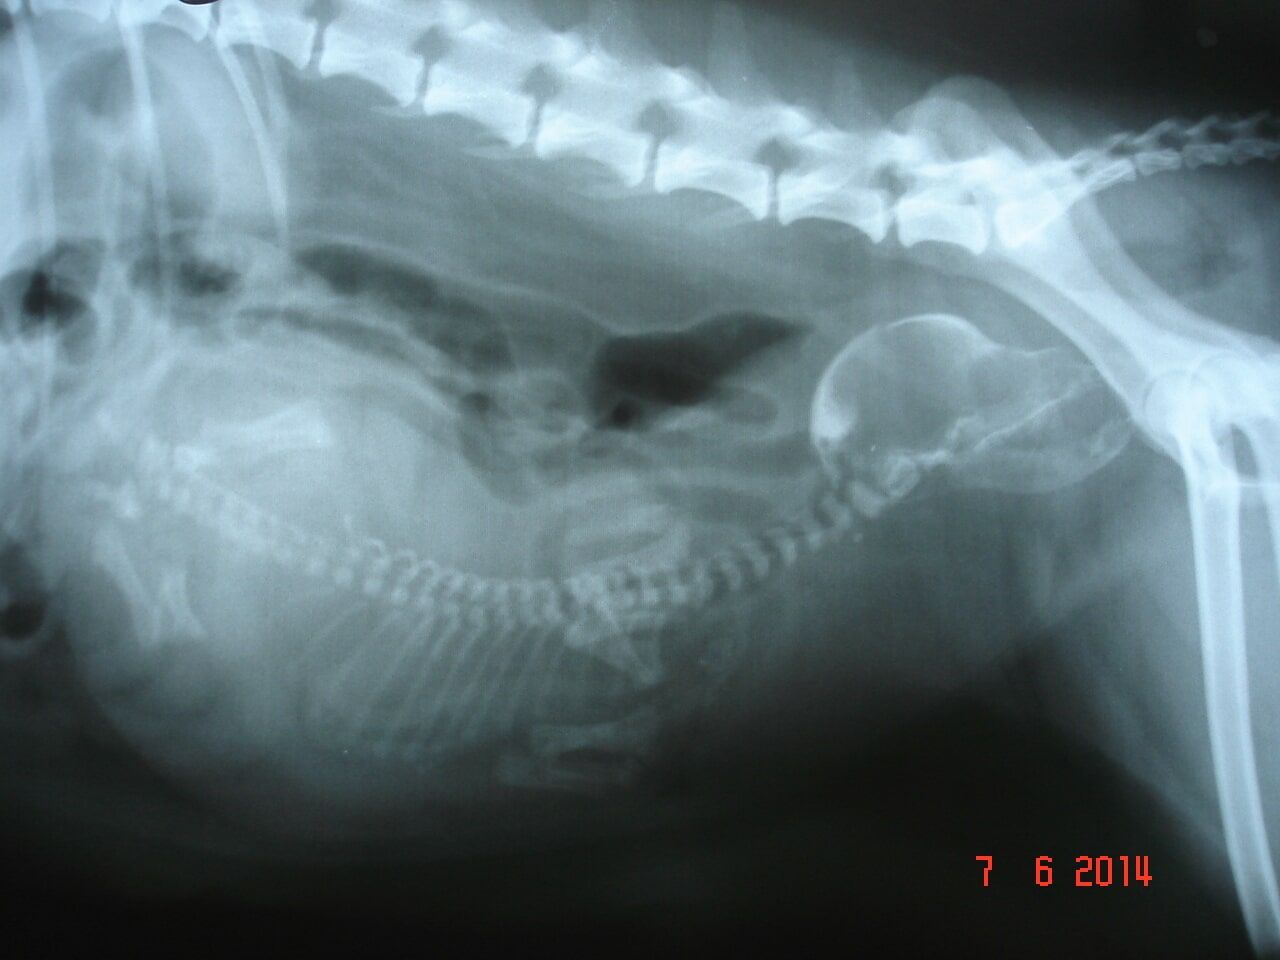

Μαιευτικό τμήμα:

Διάγνωση εγκυμοσύνης, Δυστοκία, Χρονισμός καισαρικής τομής, Διερεύνιση υπογεννητικότητας, Πυομήτρα, Διαταραχές μαστών, Νεοπλασίες γεννητικού – Μαστεκτομές